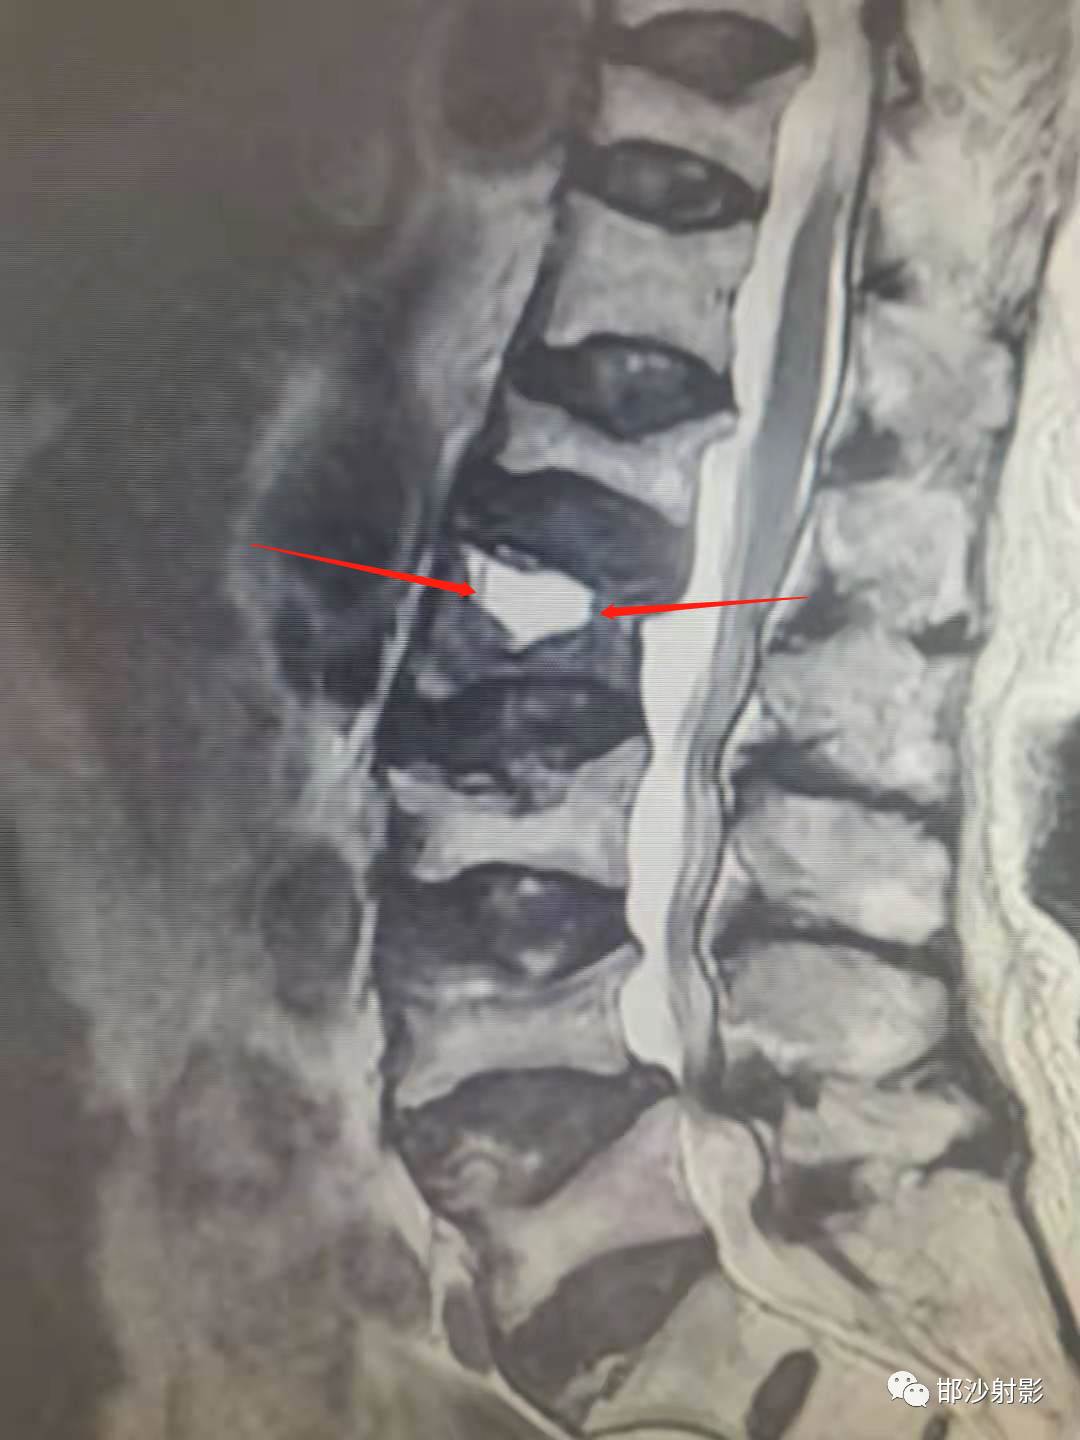

T2WI,双线征(线样高信号被低信号包绕)

真空裂隙征(IVC):是椎体缺血坏死的典型表现,前部较后部多见;IVC为渗液时,T1低信号,T2高信号,此征象称为液体征象,高度提示椎体缺血坏死,并可用于鉴别kummell与骨质疏松引起的压缩性骨折,IVC为气体时,MRI均为低信号。

Kümmell's disease(Kummell 病)病是指患者在经历无明显症状期的轻微外伤史后,数月至数年间出现症状复发、加重甚至脊柱后凸畸形的一种疾病。该病主要发生于骨质疏松的中老年患者,以男性稍多,青少年患者非常罕见。在该病的临床诊疗过程中,影像学检查十分重要,X线平片中的椎体内真空裂隙开口现象以及 MRI 检查中的双线征均可用来辅助诊断。

目前关于 Kummell 病影像学表现尚存在争议,暂无统一的影像学诊断标准,IVC、开口现象、双线征为其重要的影像学表现,但均缺乏特异性。而放射性核素骨扫描、SPECT对病变性质不明确或考虑恶性情况时,具有较高的应用价值,在今后的研究中若能将放射性核素骨扫描、SPECT与常规影像学检查结合起来,或许对确立Kummell 病影像学诊断标准有很大的推动作用。